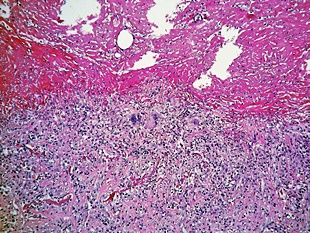

늑막에 생기는 염증으로 건성과 습성으로 나누어지는데요. 건성 늑막염의 경우 늑막에 섬유소가 침착되며, 습성 늑막염은 늑막강 속에 삼출액에 고이는 현상이 있어요. 화학요법으로 완치가 가능하며 심한 운동이나 과로가 원인이 되는 경우도 있다고 해요.

독감과 같은 바이러스에 의해 유발되는데요. 폐렴 폐혈전, 폐색전증에 의해서 발생되기도 합니다. 그 외에도 악성 종양, 류머티즘성 관절염, 루푸스와 같은 자가면역 질환에 의해 발생되기도 하는데요. 드물게 극심한 운동이나 키가 급성장하여 생기는 사례도 볼 수 있어요.